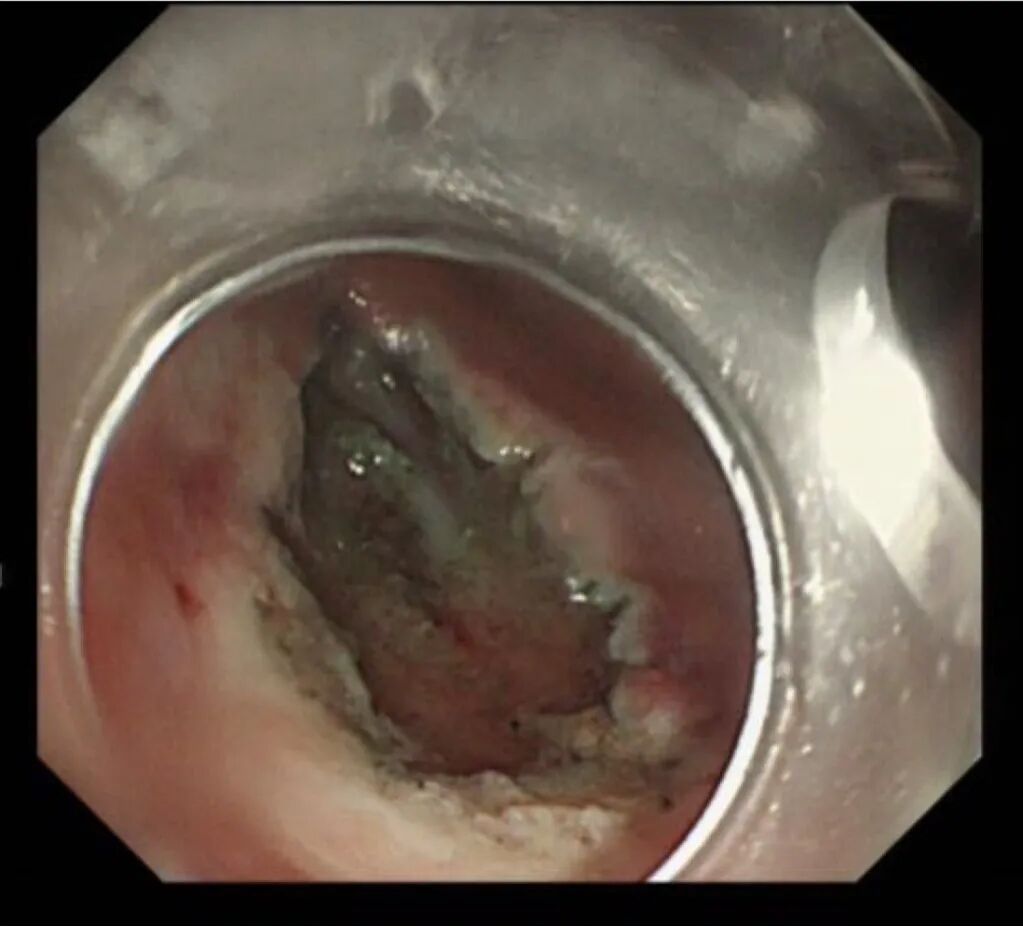

孙某某,女,65岁,因间断上腹痛10余天完善胃镜检查,胃体上段见两处直径0.5-0.8cm黏膜下隆起,超声内镜见病变起源于固有肌层,呈低回声改变,截面大小5.5*6.0mm。

考虑间质瘤,因有增大并恶变的风险,与患者家属详细沟通、解释病情,完成充分的术前评估及准备后,孙院长实施内镜下胃全层切除术,成功将病灶切除;术后病理诊断示“胃间质瘤,患者康复出院”。